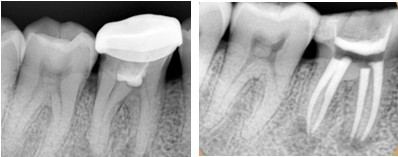

1、根管治疗是分牙位收费

一般情况下分为3大类:前牙、前磨牙(双尖牙)和磨牙。其中前牙根管治疗价格最低,然后就是前磨牙,后磨牙最贵。

2、根管治疗按牙根收费

一般情况下我们的前牙只有1条牙根,而我们的磨牙则有3-4条牙根,因此治疗起来也会更麻烦更耗时间。

3、根管治疗按复杂程度收费

一般情况下初次根管治疗比二次光管治疗费用相对较低,第二次进行根管治疗不仅手术难度大,所以二次根管治疗费用会更高。